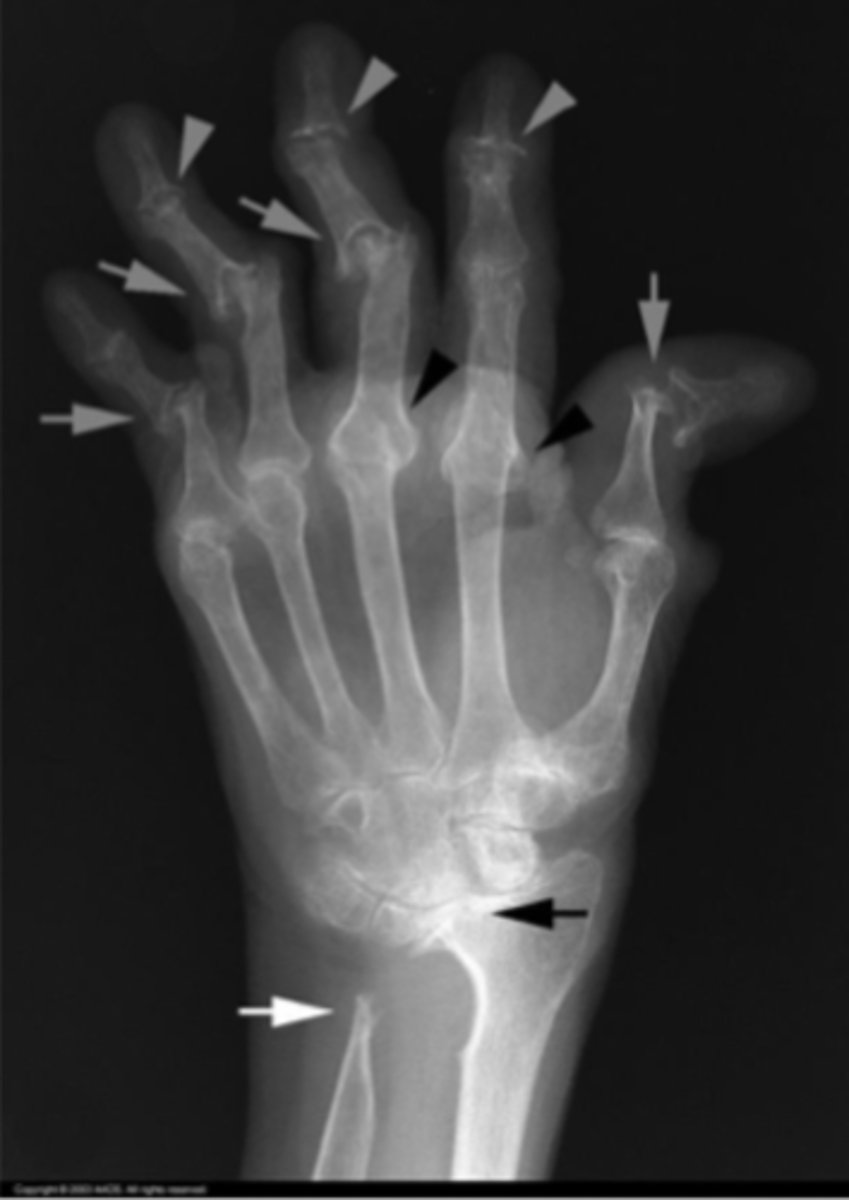

Arthritides

What is the issue?

rheumatoid arthritis